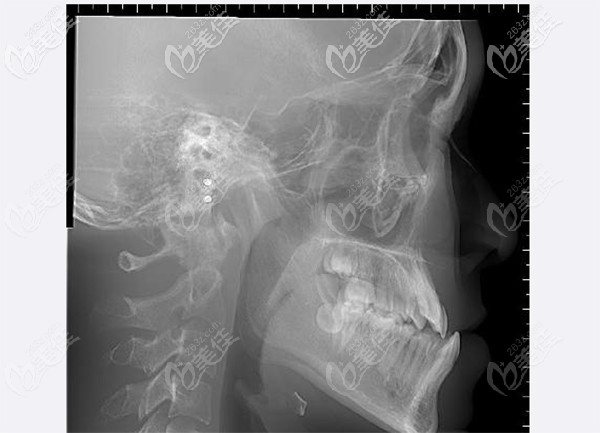

然后给孩子拍了CT后,症状就更加明显了。下颌突出,明显看出有地包天的情况。

医生根据孩子反颌比较严峻的情况,给的矫正方案是先拔掉下颌两个前磨牙,上颌左侧重叠在一起的虎牙和侧切牙想办法排齐。